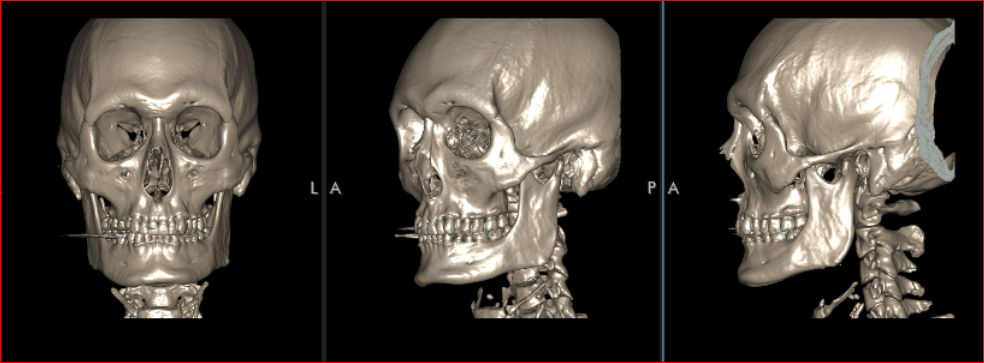

@thecel why don't u do some cool shit and morph people's skulls in blender charging them for it so they know what surgeries to get? correct me if this is a bad idea idk how u would convert DICOM CBCT to blender but i saw Giant do it and i think you could do it well

Looking at this slice through my zygos I think my maxilla is flat.

But comparing my side profile to your chart it seems not flat.

I might just be on the borderline for flat. I’m certainly recessed but it appears to be mostly in the lower maxilla as my anterior nasal spine is set back from my upper nasal bone.. I don’t see how Lefort 2 alone would be good here, it would have to be segmental 2 and 1 combined.

It also raises a question about infraorbital implants because unless you already have an exemplary “3D” maxilla, they are going to flatten it out even more. I’m not sure my face can support them at all without Lefort 2.